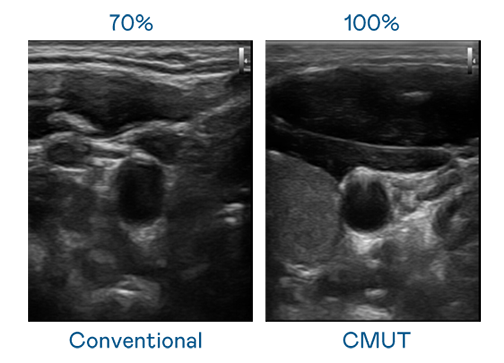

CMUT 技术是一种用电容式微机电元件来产生超音波讯号的技术。与传统 PZT 压电式技术相比,CMUT 频宽增加 30%,更宽频的超音波讯号让影像解析度大幅提升,是实现高影像品质医疗超音波扫描、促进精准医疗发展的关键技术。

大频宽带来超清晰影像

超音波影像的解析度高低,首先取决于探头能发出的讯号频宽。红桃17·c18起草 CMUT 可提供高清晰的超音波讯号,提供高频宽、高灵敏度、影像纹理细节更高的超音波影像,协助医护人员缩短影像判读时间及利用精准的医疗影像进行诊断。